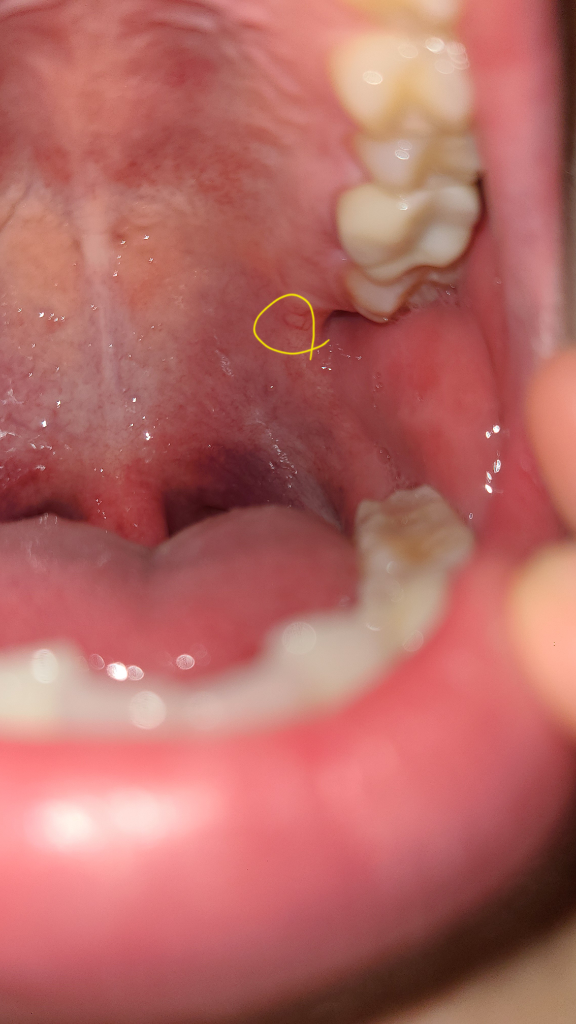

"노란색"으로 표시된 게 "1월 1일"에 찍은 사진이구요

"빨간색"으로 표시된 게 오늘 "1월 12일"에 찍은 사진입니다 현재 재수학원에 다니고 있어서 계속 피곤한 상황이긴 합니다 이번주에 이비인후과에서 탄툼액을 받아서 한 이틀-3일 끊어서 사용했는데도 별다른 차도가 없는 거 같은데 조직검사 받아봐야 하나요?

• 1번 째 사진

• 2번 째 사진